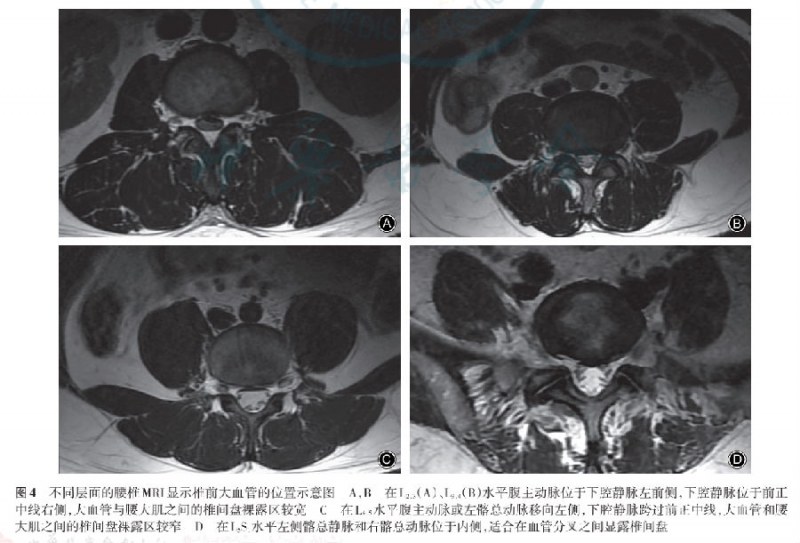

腰椎MRI T2加权横截面上观察提示腹主动脉位于下腔静脉左前侧,在L2-3、L3-4节段腹主动脉左缘分别距椎间盘前中线14.9±5.1mm、13.9±4.6mm,下腔静脉位于中线右侧,大血管和腰大肌之间的椎间盘裸露区距离较宽。

在L4-5水平,腹主动脉或右髂总动脉左缘距椎间盘前中线19.7±5.9mm,下腔静脉跨过中线,静脉左缘距椎间盘前中线4.6±8.7mm,大血管和腰大肌之间的椎间盘裸露区距离较窄。

在L5-S1水平,椎间盘位于血管分叉之间,处于内侧的是左侧髂总静脉和右髂总动脉,其内缘分别距椎间盘前中线14.6±6.8mm、17.6±5.3mm(表2,图4)。